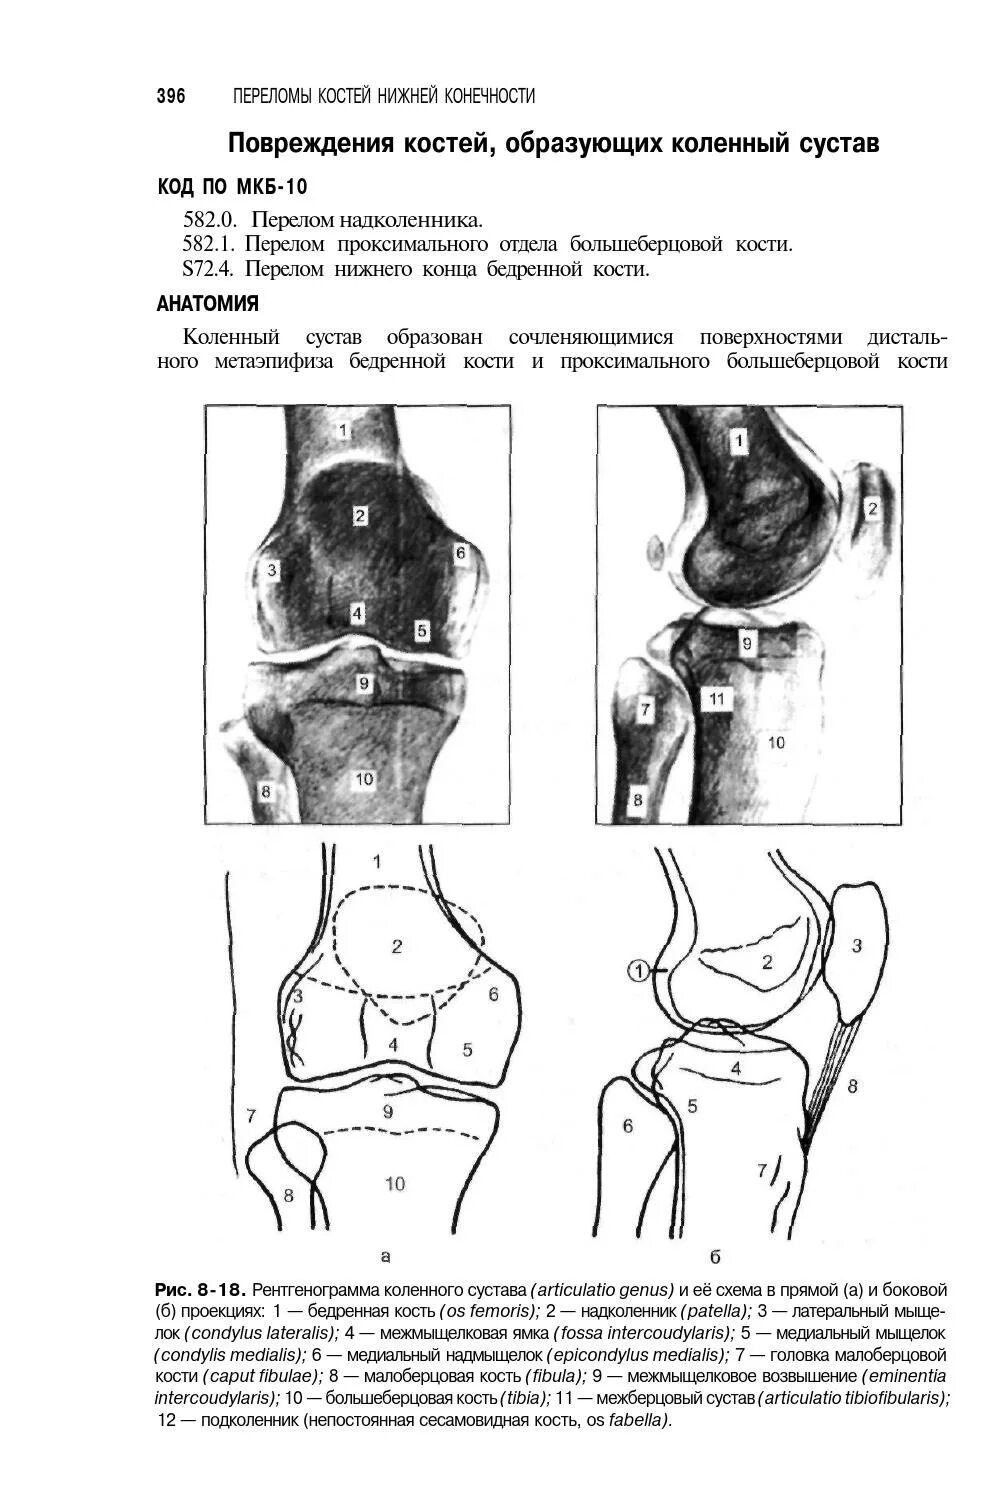

Чрезмыщелковый перелом мкб